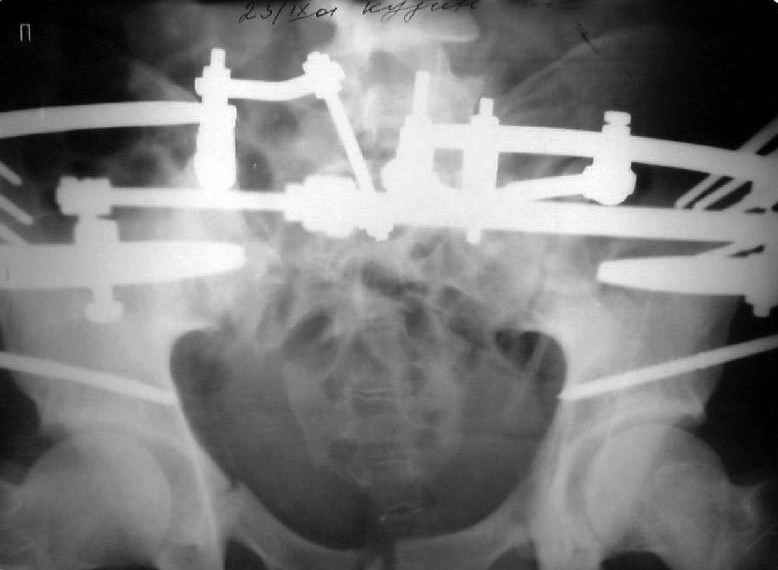

Мы, как правило, в подобных случаях проводим оперативное лечение в несколько этапов. Первым устраняем деформацию при помощи АВФ (кольцевой конструкции с фиксацией задних отделов), вторым- выполняем введение илиосакралых винтов, накостный остеосинтез передних отделов.

Для информации к размышлению о возможности исправления имеющейся деформации предлагаю похожий случай.